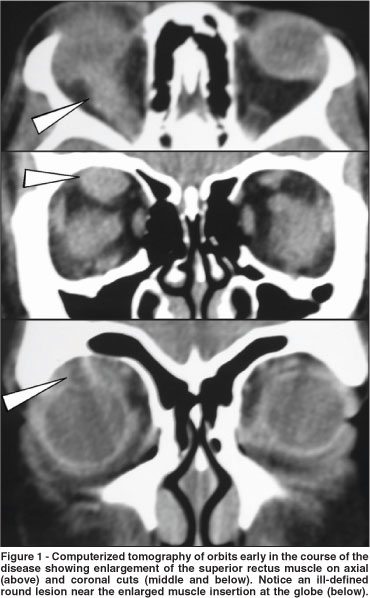

Because of the atypical restriction on downgaze and unresponsiveness to corticosteroid treatment, imaging studies were reviewed. Computerized tomography (CT) scans disclosed a small cystic round lesion associated with a marked superior rectus muscle enlargement that had been present in two previous CT scans but had been overlooked (Figures 1 and 2). No other abnormalities were found on imaging or laboratory investigations. An excision biopsy was indicated and carried out through a right upper fornice conjunctival incision. At surgery a cyst was found near the insertion of the superior rectus muscle. Its mucoid content and capsule were sent to histopathological study that confirmed the diagnosis of cysticercosis infection. A parasitologic examination was negative, and oral steroids were gradually tapered and removed. Right eye restriction improved partially, remaining a 20 diopter right hypertropia with a 15 diopter exotropia when fixing the left eye in Prisma and Cover Test.

Imaging studies such as B scan ultrasonography, magnetic resonance imaging and CT scan can be helpful especially when a cystic formation or calcification inside the muscle is documented. Such findings however, may be very discrete and overshadowed by the marked enlargement of the muscle, usually extending far beyond the cyst, as it occurred in our case (Figures 1 and 2).